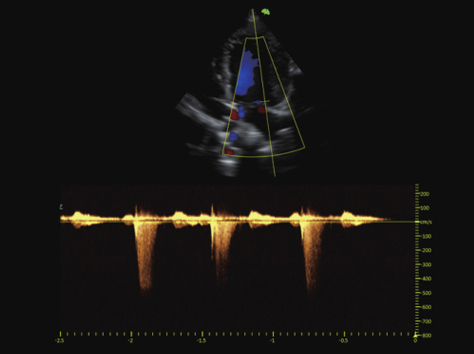

在心脏异常反流病例中,反流束的流速往往都很高,一般的频谱难以捕捉到高速反流信息,此时高灵敏度的连续多普勒成像就显得特别重要了,它可以捕捉到更高的反流束度,给临床诊断提供有力依据。